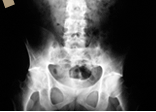

40세 이하 젊은 나이에 아침에 심해지고 활동 후 좋아지는 요통이 3개월 이상 지속되는 환자의 병력, 골반 압박시 통증과 척추 및 흉곽의 운동 범위와 같은 진찰 소견, 그리고 천장 관절의 경화 및 요추가 대나무처럼 굳은 방사선 소견으로 진단을 하게 됩니다. 그래서 어떤 피검사나 방사선촬영만으로 진단을 하는 것은 아닙니다.